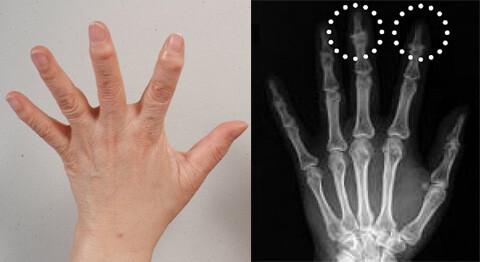

사진설명

손가락 관절에서 벗어나려면 항문~골반~등뼈~엘보우~손목 순서로 뼈 속 산화철을 제거해주어야 한다. 아울러 아랫배를 다스려주면 보다 손쉽게 해방된다.